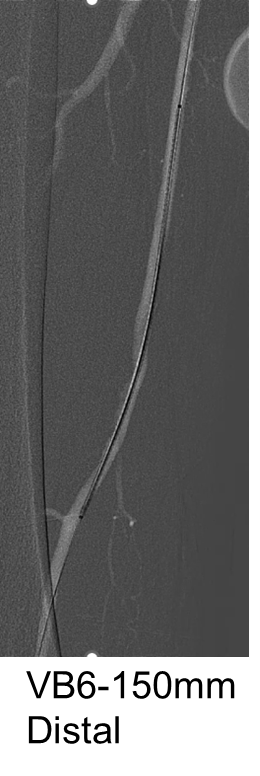

支架植入:遵循“由远及近”原则,先放置远端 DES,再覆盖中段 VB,最后处理近端。利用 Eluvia 的可调节性优化重叠。

后扩:常规使用 6mm 高压球囊进行后扩张,确保支架充分贴壁和管腔获得。